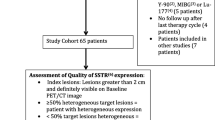

A total of 31 subjects (14/31 females (45.2 %), mean 60 ± 10 years (y), range, 39–79 y) of four university medical centers with histologically proven pNET were enrolled. The patients enrolled in the present subanalysis were part of a larger patient cohort [13]. The study population was restricted to G1/2 pNET, as G3 tumors normally suffer from rapid disease progression under PRRT [17]. Ki67 ranged between 1 and 20 % with a median of 5 % for the entire cohort (n = 31). Eight out of thirty-one (25.8 %) were classified as G1 NET and 23/31 (74.2 %) as G2 NET. In G2 NET, the median Ki67 was 8 % (range, 4–20 %).

Analysis of CgA levels before PRRT revealed a range between 35 and 64.700 μg/l (median, 924 μg/l). Twenty-five out of thirty-one (80.1 %) patients were pre-treated (somatostatin analogs, n = 19/31, (61.2 %); surgery, n = 13/31 (41.9 %); chemotherapy, n = 9/31 (29 %); and external beam radiation, n = 1/31 (3.2 %)). Clinical characteristics of the patient cohort are given in Table 1.

PRRT was performed with a mean of 7.2 ± 1.0 GBq (194.6 ± 27 mCi; range, 3.3–8.9 GBq, 89.2–240.5 mCi) per cycle using [177Lu]DOTATATE. In total, the enrolled subjects underwent 112 treatment cycles (median, 4, range, 1–6; mean 3.6 ± 1.2) aiming at a standard interval of 3 months on a compassionate use basis [18, 19]. The majority of cases (21/31, 67.7 %) received at least four subsequent treatment cycles. PRRT was performed according to The joint IAEA, EANM, and SNMMI practical guidance on a compassionate use basis or in accordance with the Rotterdam protocol as published by Kwekkeboom et al., i.e., at time point of disease progression [18, 19]. Long-acting and short-acting release formulations were also discontinued according to [18]. Imaging including both functional (SSTR-PET) and/or morphologic imaging (CT) modalities was performed every 3–6 months after PRRT [18, 19].

rogression-free survival (PFS) was defined according to Response Evaluation Criteria in Solid Tumors 1.1 (RECIST1.1) by follow-up examinations starting from the time point of baseline imaging [18, 20]. For the calculation of overall survival (OS), the time interval between the baseline SSTR-PET examination and date of death was analyzed.

PET/CT Imaging, Imaging Interpretation

As a prerequisite for treatment initiation, all patients had to demonstrate sufficient uptake in pre-therapeutic SSTR-PET computed tomography (CT) [18, 19], i.e., lesional uptake higher than physiological liver uptake [21]. A mean of 132 ± 35.7 MBq (3.6 ± 0.9 mCi; range, 72–185 MBq, 1.9–5 mCi) of [68Ga]DOTATATE/-TOC (n = 27, [68Ga]DOTATATE and n = 4, -[68Ga]DOTATOC) was administered intravenously. After 60 min, imaging was performed using the following scanners: Bonn, Biograph 2 PET/CT (Siemens Medical Solutions, Erlangen, Germany); Wuerzburg, Biograph 64 (Siemens Medical Solutions, Erlangen, Germany); Munich, Gemini TF PET/CT (Philips Medical, Eindhoven, Netherlands) or Siemens Biograph 64 (Siemens Medical Solutions, Erlangen, Germany); Hannover, Biograph 2 (Siemens Medical Solutions, Erlangen, Germany). System spatial resolutions are 4.8 mm for the Gemini TF, 4.4 mm for the Biograph 64, and 9.3 mm for the Biograph 2 [22,23,24]. All data was reconstructed using iterative algorithms implemented by the manufacturer and depending on the routine protocol of the different medical centers. Scatter and attenuation correction was performed based on the different transmission data [13]. To allow for valid pooling of the results between Siemens and Philips PET/CT scanners, phantom studies based on the National Electrical Manufacturers Association NU2-2001 standard were conducted in Munich. According to a recent published study investigating the robustness of TF in GEP-NET patients using SSTR-PET in a multicentric setting, the following TF were taken into account [25]: from the gray-level co-occurrence matrix (Entropy, Homogeneity), from the gray-level run length matrix (high gray-level run emphasis (HGRE)), and from the gray-level size zone matrix (intensity variation, high gray-level zone emphasis (HGZE), zone length non-uniformity (ZLNU), short-zone high gray-level emphasis (SZHGE), zone percentage (ZP)). In addition, metabolic tumor volume (MTV) and total receptor expression (TRE) were assessed. Lesions were identified by reviewing the SSTR-PET, CT, and fused hybrid imaging by board-certified nuclear medicine physicians. In case of multiorgan involvement, a maximum of three lesions per organ (largest in size and metabolically most active lesion) was segmented. A manual segmentation method was preferred in order to exclude adjacent physiological SSTR-avid structures on PET/CT images [26]. TF analysis was performed by using the Interview Fusion Workstation (Mediso Medical Imaging Systems Ltd., Budapest, Hungary) [13]. As previously described, CT images were available only for localization and not used to guide delineation of the VOI [27]. Further, conventional PET parameters (SUVmean/max, metabolic tumor volume (MTV) and tissue receptor expression (TRE = MTV × SUVmean)) were also investigated [13]. The radiotracer concentration in the ROIs was normalized to the injected dose per kilogram of patient’s body weight to derive the SUVs. For the assessment of TF, 162 volume of interest (median, 5, range, 1–12 per patient) were manually segmented. In the majority of the cases (22/31, 71 %), at least four lesions were investigated. Metastases with an MTV smaller than 10 cm3 were excluded [28].